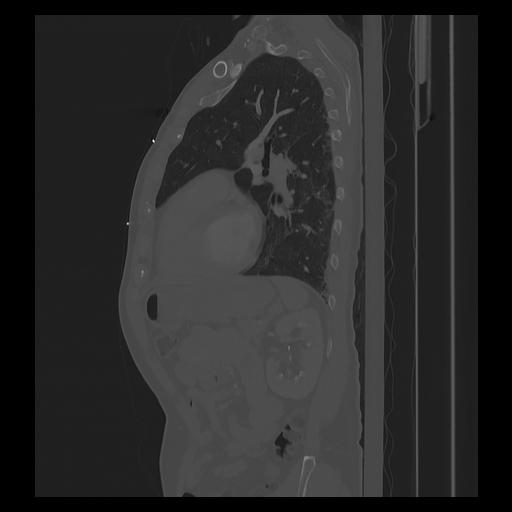

33 PULMON,CE,Sagittal,3.000,PULMON,Sagittal,